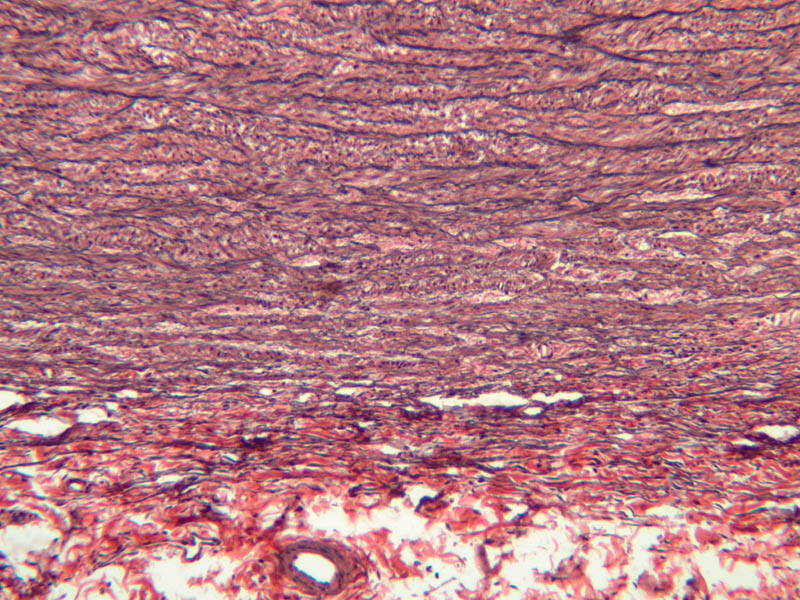

The blood is pumped from the heart into large, elastic (conduction) arteries. Examine a section of the aorta (A-26, H&E [2.5x, 10x, 20x, 40x-labeled] [2.5x, 10x-labeled, 20x, 40x]) which is a typical elastic artery. Although the tunica intima and tunica media are difficult to distinguish, note that together they are much thicker than the tunica adventitia. Using high power magnification, examine the tunica media and identify the cell types and fibers, recalling that elastic tissue appears light pink and refractive in H&E preparations. Compare this slide with a section of aorta stained to demonstrate elastic fibers (A-27, verhoeff [2.5x, 10x, 20x, 40x-labeled] [2.5x, 10x]).

Note how extensive the elastic tissue is in the tunica media. The elastic tissue is arranged in the form of numerous concentric elastic lamellae, which are cross connected by slender elastic fibers. Observe the distribution of elastic fibers in the tunica intima (A- 27 [2.5x, 10x, 20x, 40x]) and tunica adventitia (A-27 [10x, 20x, 40x]). The internal and external elastic membranes are not well demarcated in the aorta since so many elastic lamellae are present. The elasticity of the aorta allows it to expand and absorb much of the pressure during contraction of the left ventricle (i.e., systole). When the ventricle relaxes (diastole), the elastic aorta contracts, continuing the movement of blood into the medium and muscular arteries.